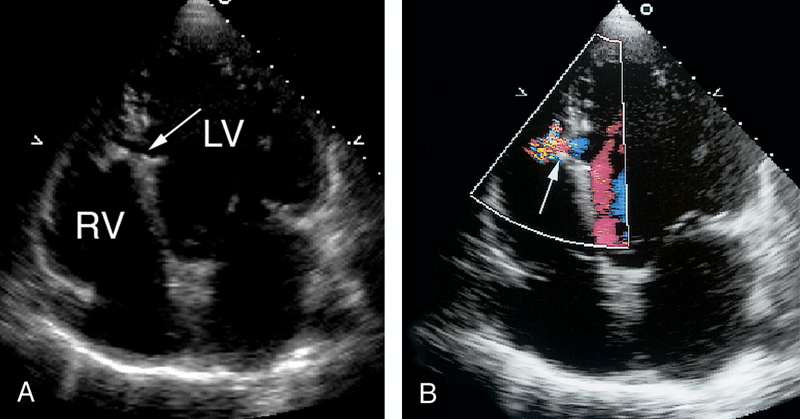

فحوصات تشخيصية لبعض امراض القلب والشرايين التاجية